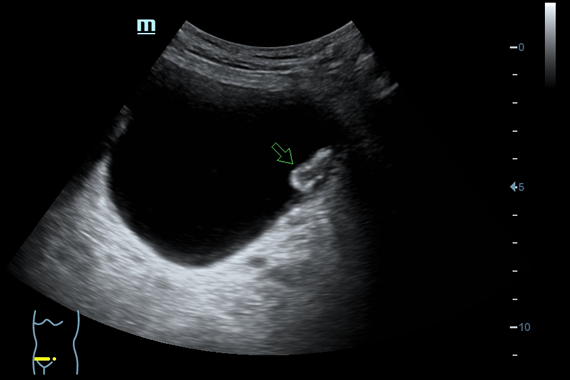

• Smart OB™ - программа автоматического расчета с возможностью ручного редактирования основных акушерских показателей: БПР, ДБ, ОГ, ЛЗР, с использованием алгоритмов автоматического оконтуривания и распознавания границ органов

• Smart NT - программа для автоматического определения и расчета толщины воротникового пространства у плода